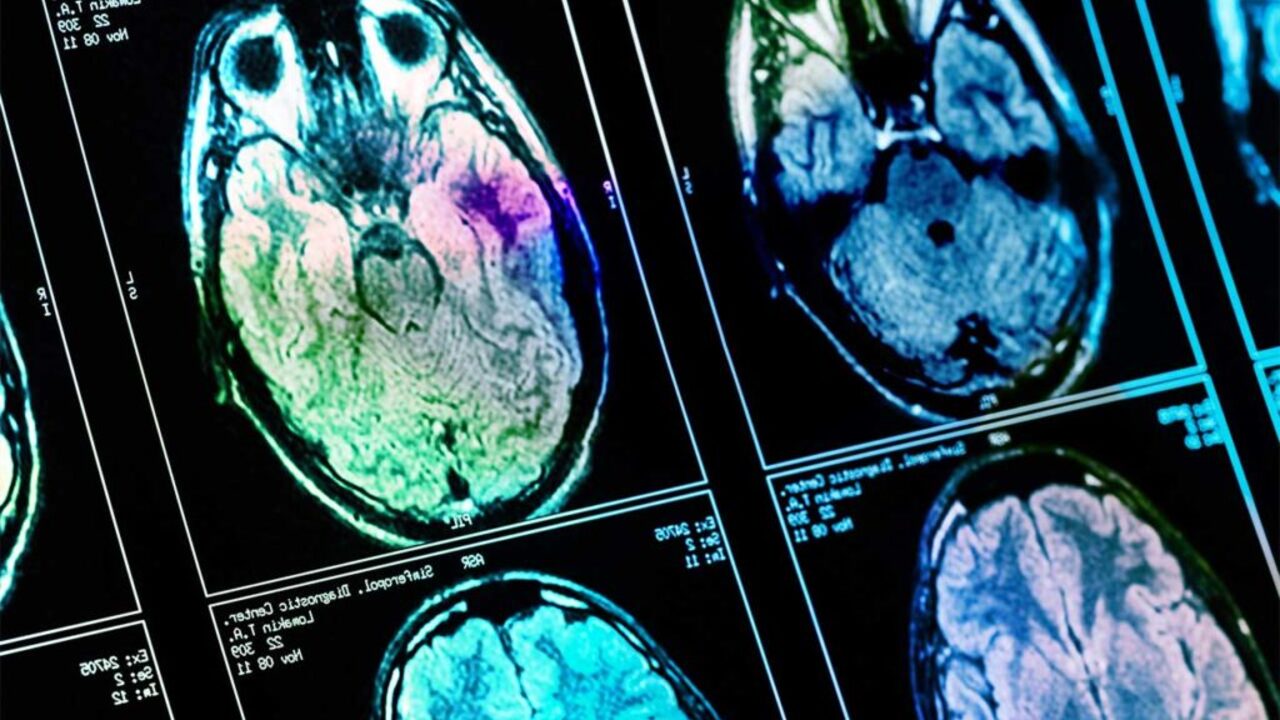

Российские учёные создали вещество, которое восстанавливает клетки мозга

Черепно-мозговые травмы сейчас довольно распространены во всём мире. Умирают от них при этом от 9,5 до 66 на 100 тысяч человек ежегодно. Однако новое вещество, разработанное учёными из Белгородского государственного университета, поможет справиться с последствиями таких травм.

Как отмечается в материале, исследователи смогли достичь ослабления вторичного повреждения мозга. Всё это благодаря веществу под названием «этилтиадиазол». Оно действует также как антиоксидант и антигипоксант (улучшает насыщение клеток кислородом).

Эффективность препарата была доказана в ходе опытов на крысах. Им вводили новое вещество за 30 минут до моделирования травмы головы.